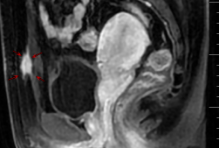

術前增強核磁共振影像

腹壁子宮內膜異位癥屬于特殊部位的子宮內膜異位癥。臨床癥狀是腹壁切口處有硬結或腫塊,絕大多數(shù)腫塊與月經密切相關,經前及月經時腫塊增大疼痛加重,經后疼痛緩解而且腫塊縮小。